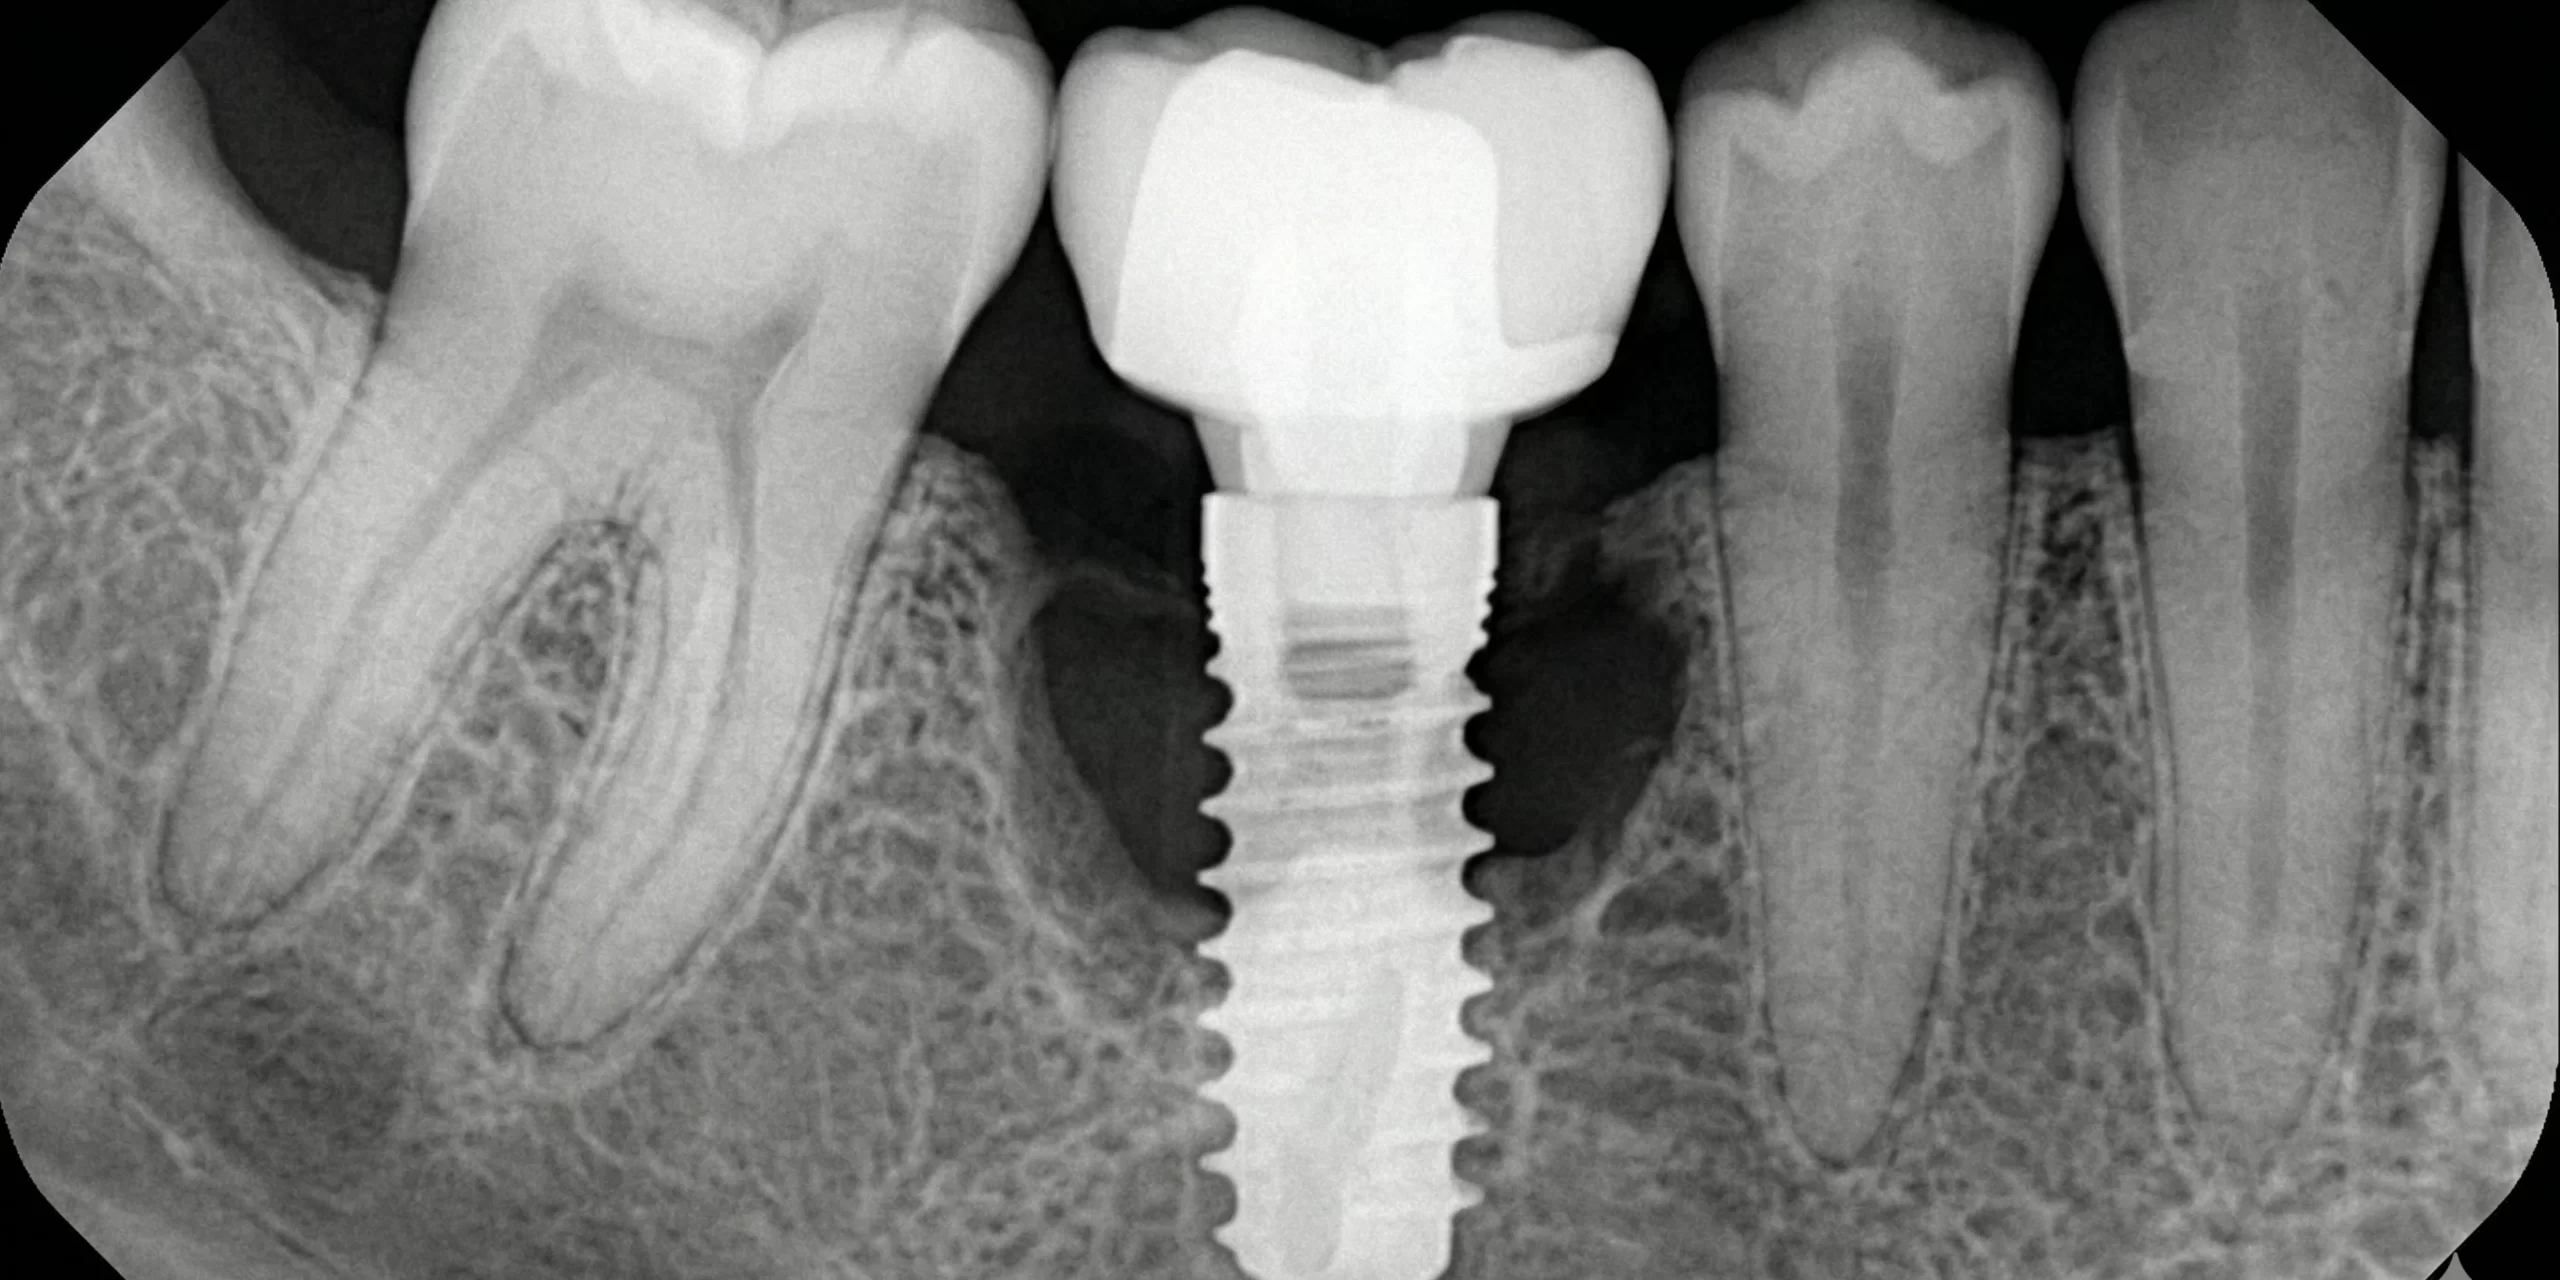

El diagnóstico exige una radiografía periapical o CBCT que permita cuantificar la pérdida ósea. Un implante que sangra al sondaje pero mantiene su nivel de cresta intacto no necesita cirugía; uno que ha perdido 3mm de hueso en 18 meses, sí.

La clasificación propuesta por Stuart J. Froum y su equipo estratifica la periimplantitis en cuatro categorías según la severidad de la pérdida ósea y la morfología del defecto:

Clase I (Temprana):

Pérdida ósea horizontal <25% de la longitud del implante. Defecto supracrestal leve.

Clase II (Moderada):

Pérdida ósea horizontal 25-50%. Defecto supracrestal con componente circunferencial incipiente.

Clase III (Avanzada):

Pérdida ósea horizontal >50% o defecto infraóseo de ≥3mm. Compromiso de la estabilidad mecánica.

Clase IV (Severa):

Pérdida ósea que supera el 50% con movilidad implantaria o compromiso estético irreversible.

Esta clasificación no es un ejercicio académico. Es un árbol de decisión terapéutica. Las Clases I y II responden a terapia no quirúrgica o quirúrgica resectiva. Las Clase III pueden intentarse con regeneración ósea guiada. Las Clase IV son candidatas a explantación.